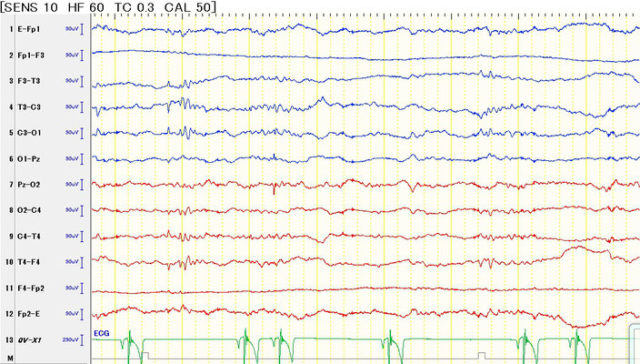

てんかん(Epilepsy)

特発性てんかん

てんかんは大脳神経細胞の過剰な興奮により様々な発作症状を起こす疾患です。

問診

血液検査

尿検査

心電図検査・血圧測定

CSF検査

などを行い除外診断しつつ、脳波検査によるてんかん性異常脳波の検出をを行うことで診断します。